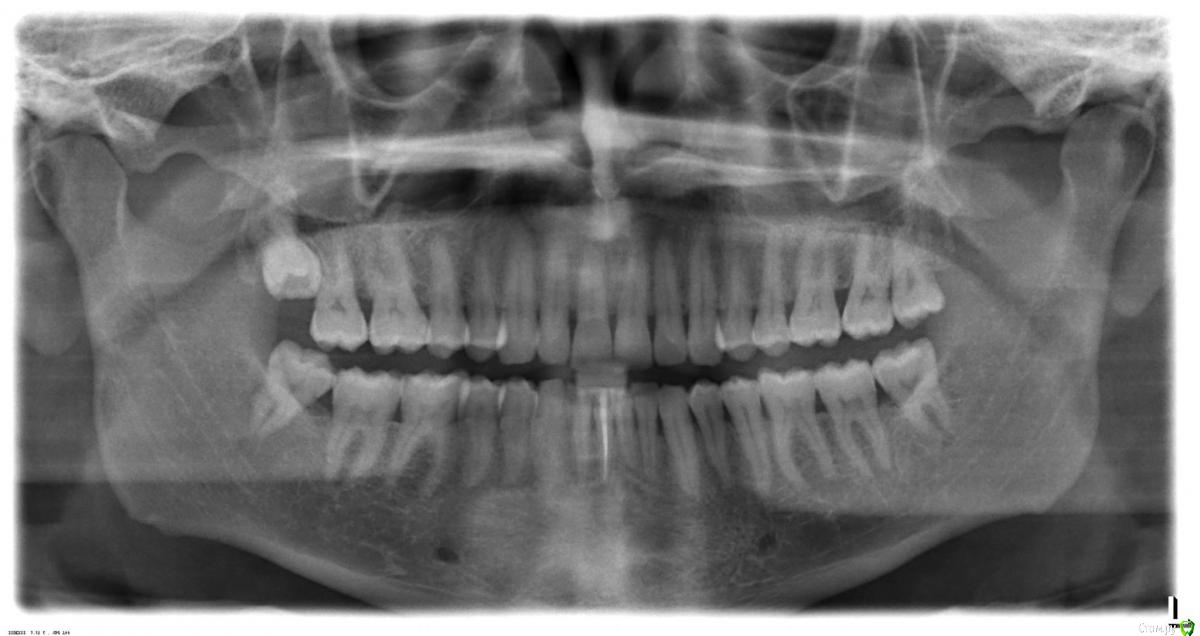

dentikl Опубликовано 22 декабря, 2016 Автор Поделиться Опубликовано 22 декабря, 2016 Потому что дефект 3-х стеночный и не выходит за границы контура челюсти,об'ем конечно кости уменьшаетсявот этот случай требует мембраны и индуктора?Ретроградно пломбировать даже если пройду на ревизии? Ссылка на комментарий

dentikl Опубликовано 22 декабря, 2016 Автор Поделиться Опубликовано 22 декабря, 2016 Зачем тогда вообще резекция!!!?там я фотки повесил.с Вашей точки зрения индуктор и мембрана нужны(Вы бы использовали в этом конкретном случае?) Ссылка на комментарий

Доктор Добрых Дел Опубликовано 22 декабря, 2016 Поделиться Опубликовано 22 декабря, 2016 В области 11 случайно не трещина корня? Медиально очаг деструкции как-то намекает на это 1 Ссылка на комментарий

Тимур86 Опубликовано 22 декабря, 2016 Поделиться Опубликовано 22 декабря, 2016 киста сбоку говорит о том что в корне скорее всего трещина Ссылка на комментарий

Bier Опубликовано 22 декабря, 2016 Поделиться Опубликовано 22 декабря, 2016 не трещина там, а латераль скорее всего. Так высоко корень только от удара может сломаться. dentikl методика РВК применяется только при невозможности или безуспешности ортоградного лечения. Т.е. в вашем случае оперировать не нужно, нужно ждать излечения. Если же вы проводите РВК - единственным смыслом этой операции является установка апикальной пломбы, желательно не короче 3-4мм вглубь канала. Прорут, Триоксидент, IRM, или биокерамика - подходят для этих целей. 4 Ссылка на комментарий

dentikl Опубликовано 22 декабря, 2016 Автор Поделиться Опубликовано 22 декабря, 2016 киста сбоку говорит о том что в корне скорее всего трещинаСори.Я дал неудачный вид Ссылка на комментарий

dentikl Опубликовано 22 декабря, 2016 Автор Поделиться Опубликовано 22 декабря, 2016 не трещина там, а латераль скорее всего. Так высоко корень только от удара может сломаться. dentiklметодика РВК применяется только при невозможности или безуспешности ортоградного лечения. Т.е. в вашем случае оперировать не нужно, нужно ждать излечения. Если же вы проводите РВК - единственным смыслом этой операции является установка апикальной пломбы, желательно не короче 3-4мм вглубь канала. Прорут, Триоксидент, IRM, или биокерамика - подходят для этих целей.корни и коронковые настолько выработаны по толщине предыдущими реставрациями,что я не могу вести их терапевтически до победного конца.Ревизия-вкладки-временная реставрация-хирургия.Резекции здесь будут только в случае,если верхушки помешают работе.Теоретически я понимаю-мембрана не нужна.Но столкнулся с заметкой на чьем то сайте и возник вопрос.Все советы-очень логичны.спасибо всем. Ссылка на комментарий